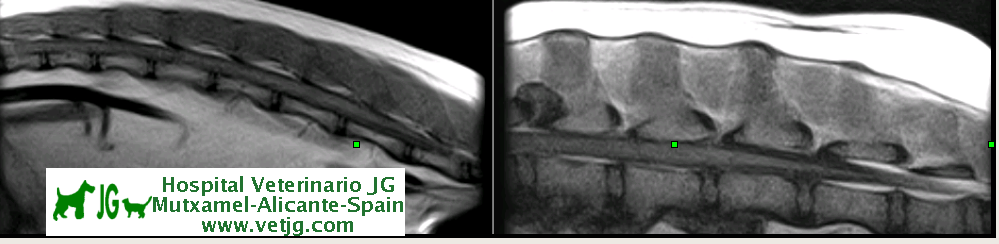

Resonancia magnética lumbo-sacra de pastor alemán |

La médula espinal acaba en L5, donde empieza la cola de caballo |